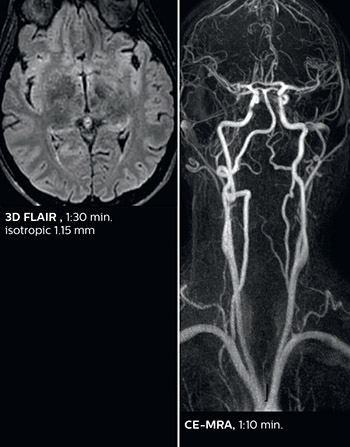

The abbreviated MS protocol for brain is only around 9 minutes, so in case of suspected multiple sclerosis, one or two more advanced sequences may be added, such as PSIR (phase sensitive inversion recovery) or susceptibility-weighted sequences to help us make more confident diagnoses in these inflammatory cases.

In this example, the optional 3D multishot susceptibility weighted sequence with 0.6 mm isotropic voxels is 2 lesions with a central vein sign (arrows) and one lesion with a phase-rim sign (arrowhead). The total scan time, including SmartBrain and axial PD/T2 3mm, is 11:10 min. and is 18:30 min. with the optional 3D PSIR and 3D SWI multishot included.

“We used to have long examination times for certain types of patients, a few lasting more than 40 minutes,” says Dr. Savatovsky. “What is remarkable, is that now all these examinations are below 30 minutes, which opens up opportunity to add more sequences when needed. It’s really hard to keep a patient for more than 40 minutes in the scanner, but because we have now cut scan times by at least 10 minutes, we can add more sequences without making the exam too long. And this is where the new system helps us make a difference. Examples include our examinations for informing brain tumor classification or giant cell arteritis workup, or for intracranial wall imaging – so in patients where we need several advanced sequences or high resolution sequences.” “We added three additional sequences in our brain neoplasm classification exam: a 3D SWI sequence, APT and ASL on top of 3D morphologic sequences, an isotropic DSC (dynamic susceptibility contrast) and multivoxel spectroscopy. I think that in patients that need a classification for brain mass, for example, we can provide a more detailed and confident diagnosis than before, allowing the clinicians to decide for either a medical workup if no tumor is suspected, or for neurosurgery as soon as possible if a neoplasm is suspected.” “In multiple sclerosis patients, we increasingly include a multishot susceptibility sequence [3] in our routine cases, thanks to the shorter scan times. Our abbreviated MS protocol for brain is around 8 to 9 minutes, so we can ask for one or two additional sequences to visualize the central veins, or to get an additional contrast to better depict posterior fossa lesions. In cases of white matter lesions of unknown significance on FLAIR images, for example when we see high signal hyperintensities in the brain, we can add on more advanced sequences such as PSIR (phase sensitive inversion recovery) or susceptibility-weighted sequences to help us in distinguishing between MS and nonspecific or vascular abnormalities in these inflammatory cases.”